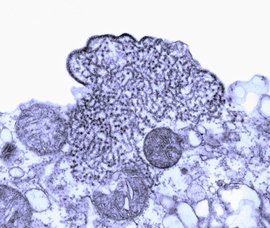

立百(Nipah)病毒,是根据1998年在马来西亚首先分离出该病毒的地点命名的。它与1994年在澳大利亚被首次分离出来的亨德拉(Hendra)病毒同属副粘液病毒科。副粘液病毒是一群有膜的RNA病毒,会导致动物与人类感染,其成员还包括人类副流行性感冒病毒、麻疹病毒等。立百病毒开始被称为类亨德拉(Hendra-like)病毒,但它与Hendra不同种,它们之间约有16%不同〕。

立百病毒(类亨德拉病毒)根据马国及美国亚特兰大疾病控制和预防中心的专家在马国设立实验室化验病毒及到灾疫区实地高查结果,该病毒比日本脑炎更为可怕,可不经蚊虫传播,直接通过伤口和身体分泌液接触而感染,包括血液、尿液、唾液等分泌物都可传染,在人方面如有伤口与带有立百病毒的生猪肉上血液沾到,即便发生传染到人体,但人与人未见传染例。该病毒检体经美国哈佛大学的病媒蚊疾病研究单位及美国疾病控制局(CDC)分析结果,显示不是日本脑炎病毒,比较像马的痳疹病毒。对于猪只与狐狸之间是否有关联性仍在研究之中。